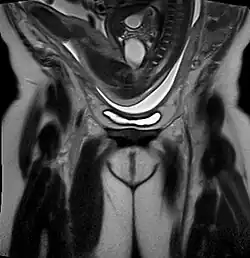

Types of breech depend on how the baby's legs are lying.[13]

- A frank breech (otherwise known as an extended breech) is where the baby's legs are up next to its abdomen, with its knees straight and its feet next to its ears. This is the most common type of breech.[19]

- A complete breech (or flexed breech) is when the baby appears as though it is sitting crossed-legged with its legs bent at the hips and knees.[19]

- A footling breech is when one or both of the baby's feet are born first instead of the pelvis.[13] This is more common in babies born prematurely or before their due date.[20]

- A kneeling breech is when the baby is born knees first.[21]